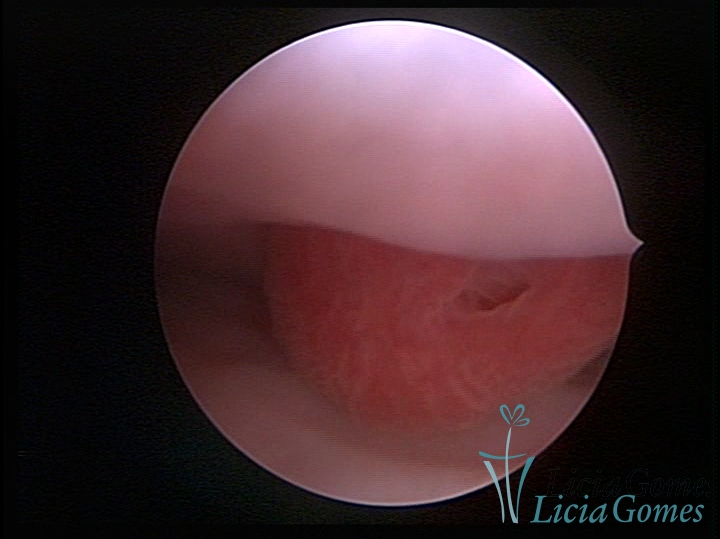

ENDOCERVICAL POLYPS

Benign tumors resulting from the reactive focal proliferation to inflammatory processes or hyperestrogenism situations, which may be sessile (with a large implantation) or stalked.